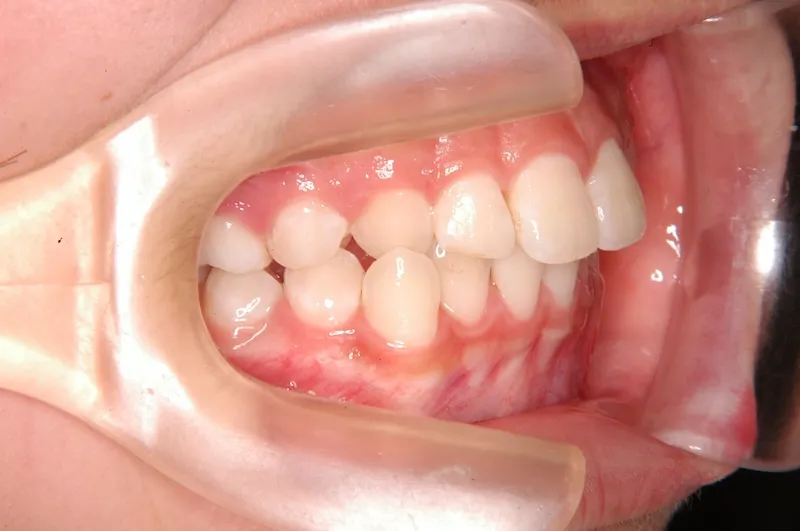

初診時年齢 小学校6年生 (女性) 主訴 犬歯がずれている・噛み合わない

診断名 叢生・交叉咬合 装置名

右下の犬歯がずれて生え噛み合わせの邪魔をしています。

噛み合わせのずれは、ぱっと見綺麗に見えますが、放っておくとのちのち噛みにくくなり、顎関節にまで影響を及ぼしかねません。

なので、見た目に関わらず噛みにくいとかんじたら、1度受診されることをオススメします。